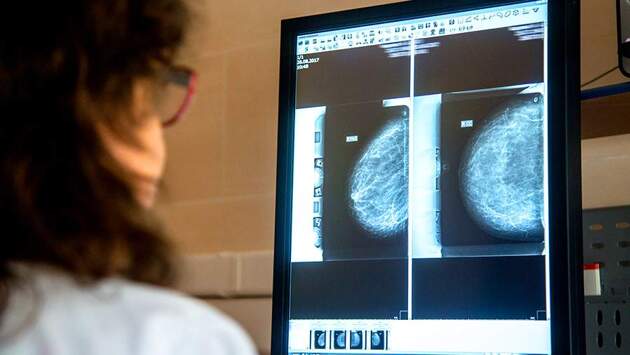

Маммография

Маммография – основной способ диагностики рака у женщин после 40 лет. Кроме того, ее стоит делать до 40, если в семье были случаи рака груди или яичников.

Врачи рекомендуют делать маммографию раз в год или раз в два года. Она позволяет выявить злокачественные опухоли на ранней стадии, и тогда лечение будет эффективным.